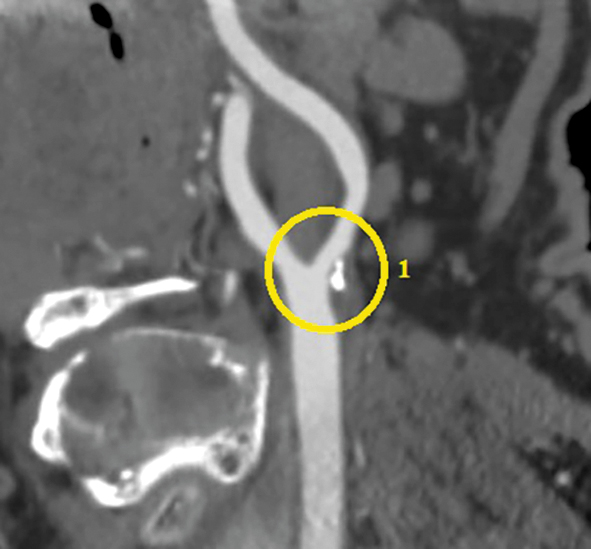

В 2020 г. пациент обратился к кардиологу с жалобами на боли в области сердца при физической нагрузке. По данным скринингового цветного дуплексного сканирования брахиоцефальных артерий и дальнейшей их ангиографии визуализирован 80% рестеноз ВСА слева (рис. 2), 97% стеноз (субокклюзия) ВСА справа (рис. 3). По результатам коронарографии диагностирован 90% стеноз ПНА (рис. 4).

Рис. 3. Ангиография правой ВСА: 1 — 97% стеноз. / Fig. 3. Right ICA angiography — 97% restenosis.